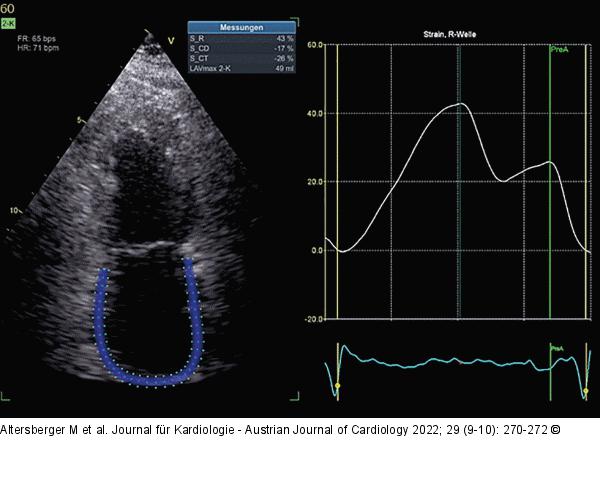

Abbildung 2: 2D-Strain

Beispiel eines normalen 2D-Strains in einem apikalen 2-Kammer-Blick. |